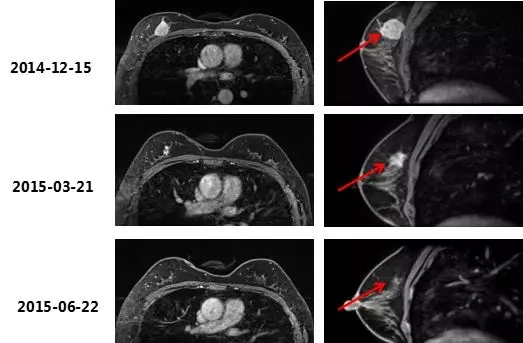

2014-12-15乳腺MRI:右乳上方占位,BI-RADS 5;右腋下少许淋巴结,部分皮质稍厚,转移待排;左乳腺体改变,BI-RADS 1。

2015-6-22乳腺MRI示:右乳上方占位NAC 8周期后,肿块较前明显缩小,几近消失,BI-RADS 6。依据RECIST 标准评价,PR。